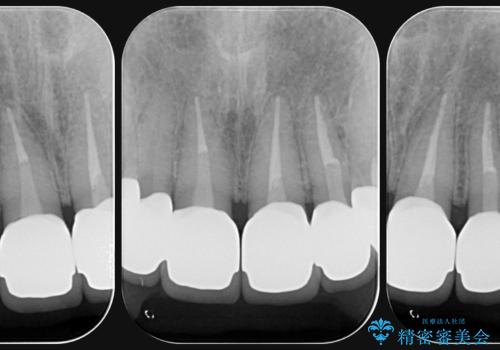

前歯には接着性の維持装置や、中途半端な形の連結クラウンが装着され、清掃性が悪く歯ぐきの腫れや、歯ぐきの形態の不揃いが認められました。

ただ、白いオールセラミッククラウンを製作・装着するのではなく、将来にわたり安定した状況を獲得するため、歯周外科を行い歯ぐきと周囲の歯槽骨の形態を整えていきます。